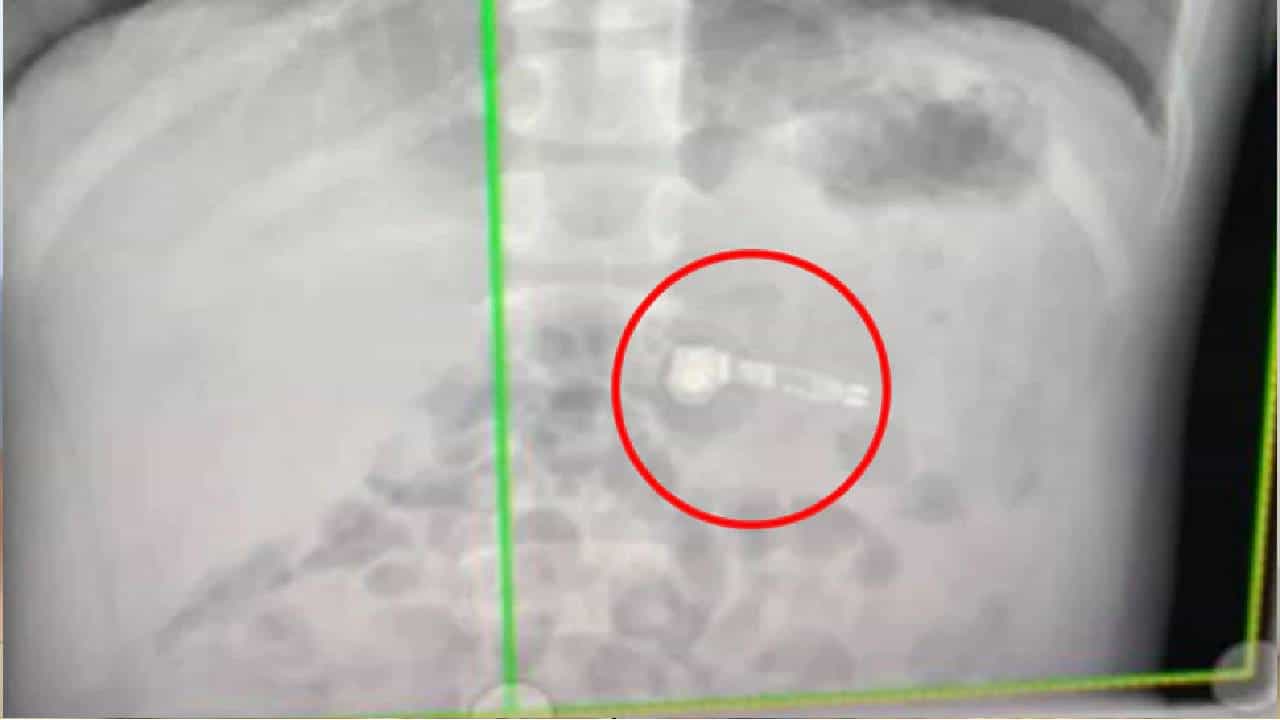

अस्वस्थ वाटू लागल्याने तिला शंका आली. मग तिने बळजबरीनं पोटात जे गेलंय ता बाहेर काढण्याचा प्रयत्न केला, पण तिला यश आलं नाही. एक्स-रे केल्यानंतर त्याच्या पोटात एअरपॉड असल्याचं तिला समजलं.